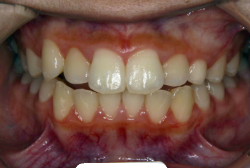

凸凹な歯並びのことを叢生といいます。矯正歯科に来院する患者様の主訴の中で、最も多いのが「配列の凸凹を真っ直ぐにしたい」というものです。歯の大きさと顎の大きさの調和がとれていないことが原因です。

凸凹を主体としたケースの場合、当院の平均治療期間は18ヶ月ですので、このケースは少し長めに経過しました。理由の一つは凸凹の程度がかなり重症だったと言うことですが、もう一つは、右下第2大臼歯が45度くらい前傾していたため、それを整直化させるために時間を要したと考えています。いずれにしても最終結果は大変よい状態と思います。

治療前は並びが乱れて見た目が悪いというのはもちろん問題ですが、歯科医学的に一番困るのは噛み合わせが悪いという点です。上下の犬歯(3番目の歯)は、上下的に離れた位置にあるため接触することができません。つまり歯としては存在していても、歯としては機能していないということです。